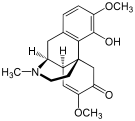

Structures

| Morphides | ||||

|---|---|---|---|---|

Codeine Codeine |

Morphine Morphine |

Oripavine Oripavine |

Pseudomorphine Pseudomorphine |

Thebaine Thebaine |